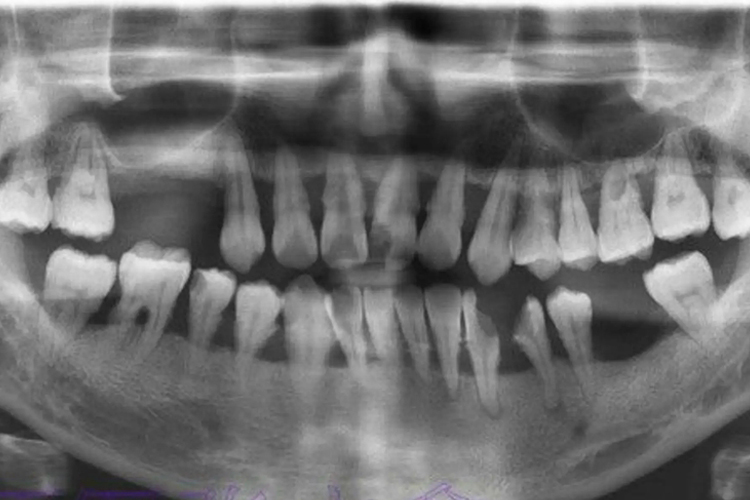

中度牙周炎牙周袋≤6mm,附着丧失3-4mm,X线片显示牙槽骨水平型或角型吸收超过根长的1/3,但不超过根长的1/2。牙齿可能有轻度松动,多根牙的根分叉区可能有轻度病变,牙龈有炎症和探诊出血,可见牙龈脓肿,也可有溢脓。